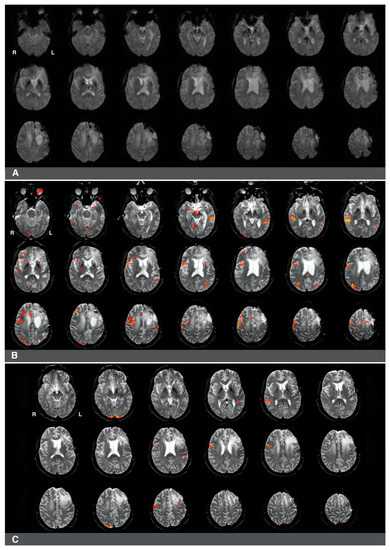

3.2. The Impact of Brain Surgery on Active Voxel Counts and Language Laterality